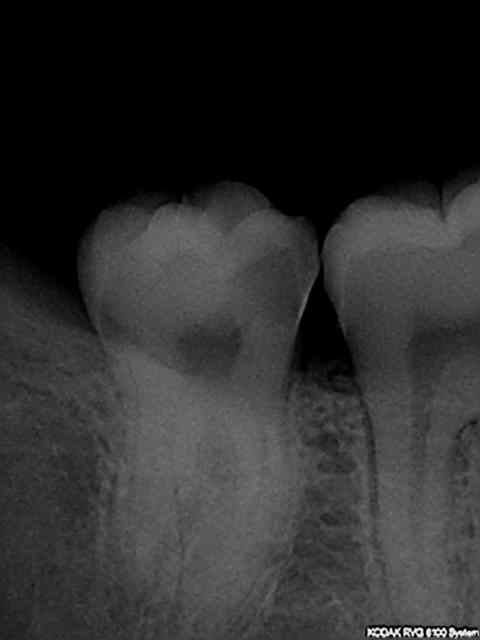

Comment peut on imaginer ne serait ce qu’un instant, qu'un tel traitement endodontique va pouvoir passer ? Et à plus forte raison, aller verrouiller le système canalaire avec un inlay core + CCM ?

ça me rend dingue ! Je viens de passer 45 ' à démonter le zinzin et c'est pas fini.

En distal de 16 sous la couronne c'est quoi ??

Pronostic assez défavorable pour cette dent, même si tu arrives à démonter tout ce tas de métal sans trop fragiliser les racines, et que tu obtiens une guérison, rien de dit que la dent durera longtemps.

Moi aussi, je fais des bouses et plus souvent que je le voudrais mais je ne vais pas couronner et bétonner un truc comme ça.

La 14 , c'est aussi la même personne.....

Quand à la 16 en distal; limite sous gingivale donc couronne mal adaptée. C'est tout.